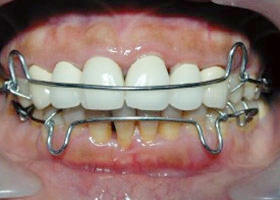

4. 使用活動式矯正裝置矯正中(矯正方式因人而異)。